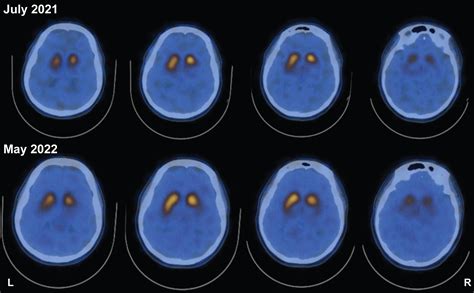

The results of a Dat Scan are analyzed by a radiologist or nuclear medicine physician who assesses the density and distribution of the tracer. In patients with Parkinson’s disease, the imaging will typically show a significant decrease in the intensity of the signal in the striatum, often appearing as a loss of the "comma" shape.

However, it is crucial to remember that this test does not provide a definitive, standalone diagnosis. It is merely one piece of a larger diagnostic puzzle. Neurologists combine the visual evidence from the scan with the patient’s clinical symptoms, family history, and physical neurological exam to reach a definitive diagnostic conclusion.

Living with the Results

Once the findings are discussed with your specialist, the next step involves integrating these findings into a management plan. If the scan suggests a dopamine-related deficit, the medical team can move forward with confidence, prescribing dopamine replacement therapies or other motor-supportive medications. If the scan is normal, the clinician may pivot toward investigating other neurological or non-neurological causes of the symptoms.